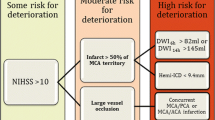

Numerous clinical and radiographic predictors of malignant cerebral infarction have been studied, though no single marker can be relied on exclusively. A 2008 systematic review of 23 published studies found that the most significant predictors were infarct size, involvement of vascular territories in addition to the MCA, low perfusion in other vascular territories, and hemorrhagic transformation [22]. Clinical characteristics that have been associated with a malignant course include younger age [9], female sex [9, 23], systolic blood pressure >180 mm Hg [24] or history of hypertension [25], congestive heart failure[25], coronary artery disease [26], leukocytosis [25], or National Institutes of Health Stroke Score severity [27, 28]. Serum protein S-100 [29], cellular fibronectin, and MMP-9 [30] are promising predictive biomarkers, though at present their clinical usefulness has not been established.

Computed tomography predictors identified include hypodensity >50 % of MCA territory on initial computed tomography [24, 25, 31], pineal displacement >4 mm within 48 h of onset [32], internal carotid artery T occlusion [28, 33], combined ICA and MCA occlusion [34], involvement of vascular territory other than MCA (eg, ACA, PCA, anterior choroidal) [25, 23], hyperdense MCA sign [31, 35], attenuated corticomedullary contrast within 18 h of onset [35], and perfusion deficit in >66 % of MCA territory at 6 h after onset [36]. MRI predictors include apparent diffusion coefficient (<80 %) [28] or diffusion weighted imaging [34] volume lesion volume >82 mL within 6 h of onset, and time-to-peak on MRI perfusion maps >162 mL [28].